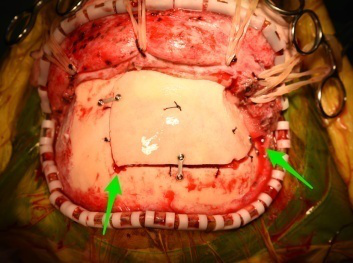

分享颅骨修补手术一例(原创)

图片尺寸4032x3024